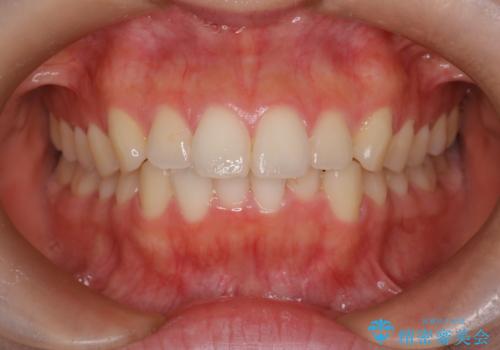

【ワイヤー矯正】八重歯 歯のでこぼこを治したい!